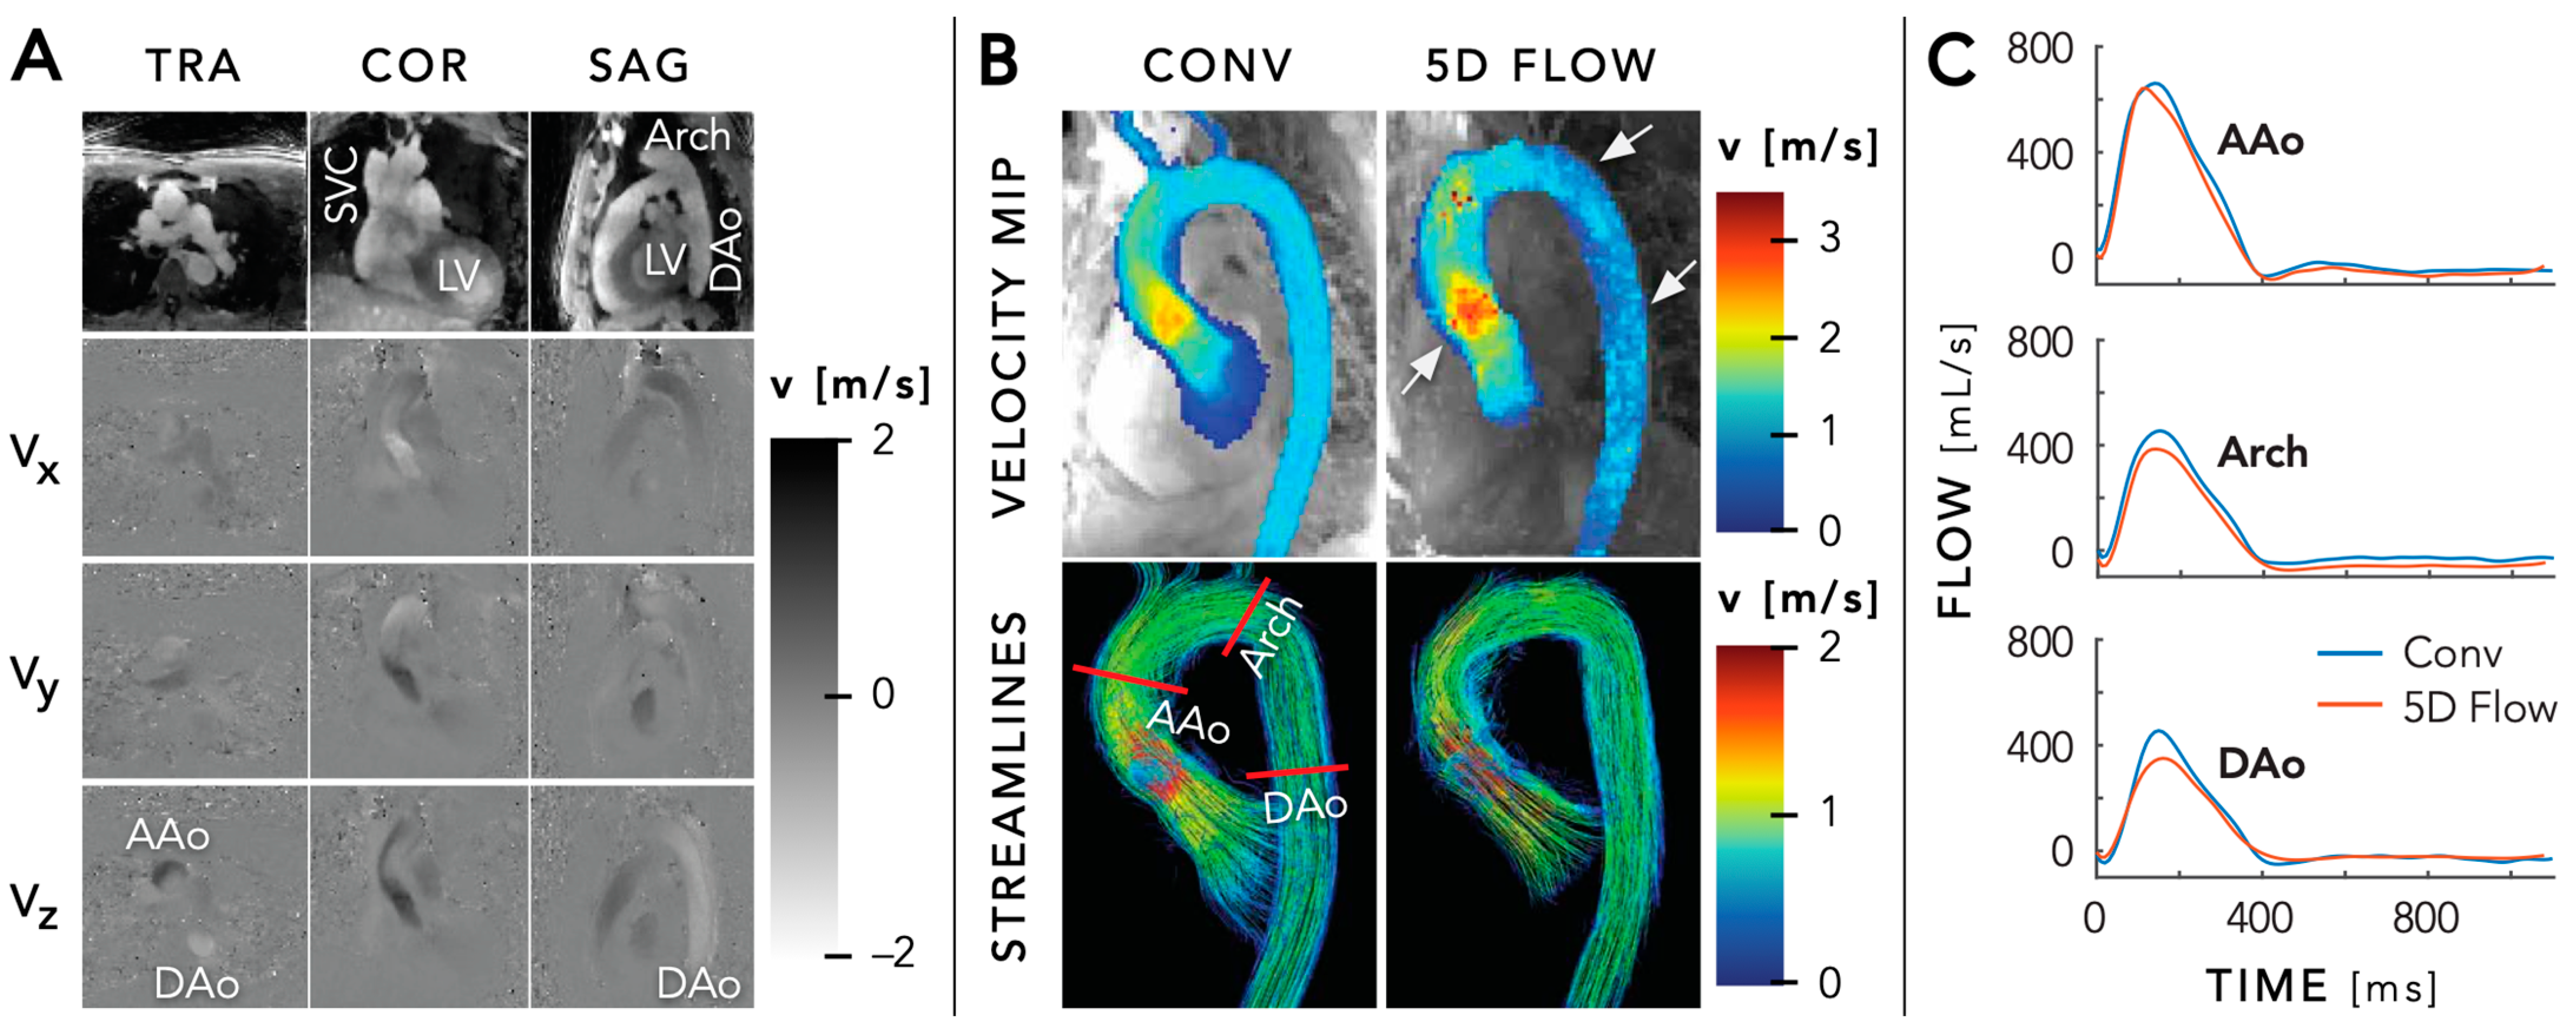

5.4. Quantitative Mapping

- Ma, L.E.; Yerly, J.; Piccini, D.; Di Sopra, L.; Roy, C.W.; Carr, J.C.; Rigsby, C.K.; Kim, D.; Stuber, M.; Markl, M. 5D Flow MRI: A Fully Self-gated, Free-running Framework for Cardiac and Respiratory Motion-resolved 3D Hemodynamics. Radiol. Cardiothorac. Imaging. 2020, 2, e200219. [Google Scholar] [CrossRef] [PubMed]